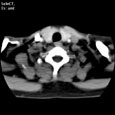

Критический стеноз правой внутренней сонной артерии. Критический стеноз правой внутренней сонной артерии

Пациент U., 69 лет

Критический стеноз правой внутренней сонной артерии.

ЦКБ5 Южной железной дороги, отделение лучевой диагностики.

На КТ-сканах шеи (до уровня основания черепа) в условиях ангиографического режима (в/в ультравист 300 - 100,0 мл 2,5 мл/сек.) определяется окклюзия правой внутренней сонной артерии на 15 мм дистальнее бифуркации общей сонной артерии, дистальнее контрастирование просвета артерии не определяется. Ассиметрично контрастированы яремные вены (справа интенсивность контрастирования значительно ниже).